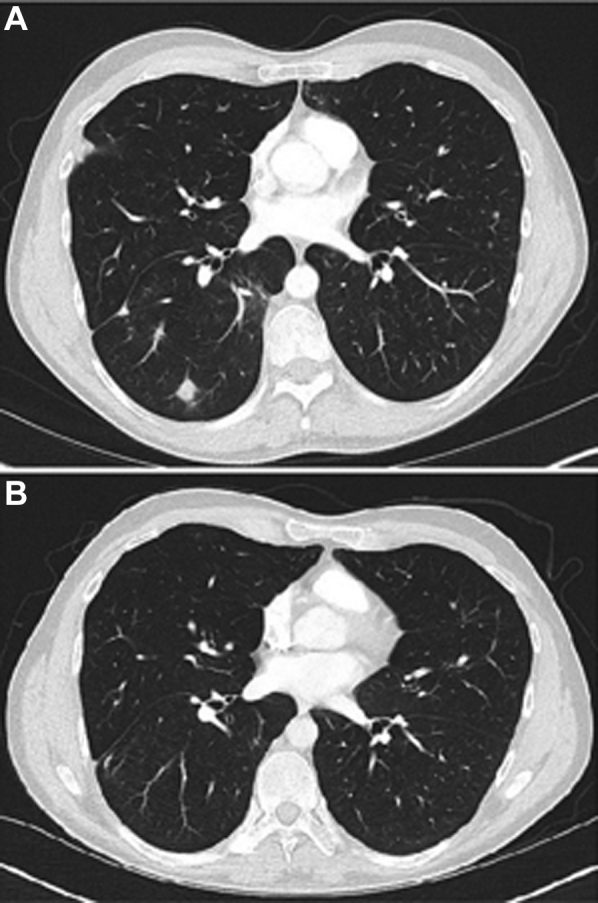

A 36-year-old man with known CVID and receiving monthly intravenous immunoglobulin therapy originally presented to the pulmonary clinic for evaluation of an incidentally noted 2-cm nodule in the right lower lobe. He underwent a right lower lobe wedge resection of the nodule with pathology demonstrating B cell-predominant interstitial lymphoid hyperplasia with frequent germinal center formation and rare nonnecrotizing granulomas, consistent with GLILD. Several months after diagnosis, he developed dyspnea at work while lifting heavy objects, and a repeat CT chest scan demonstrated an increasing number of lower lobe-predominant nodules. Pulmonary function testing demonstrated a normal diffusion capacity of the lungs for carbon monoxide, corrected for hemoglobin (Dlco[Hb]). He was started on rituximab and azathioprine but developed significant nausea and vomiting with an associated 20-pound weight loss thought to be secondary to the azathioprine, and therefore both medications were discontinued after 6 weeks of therapy. He initially noted improvement in his dyspnea, but subsequently developed worsening cough and shortness of breath. He was treated with antibiotics and steroids with some improvement in his symptoms. However, 1 year later, he re-presented to the clinic with some worsening of his shortness of breath, and a repeat CT chest scan was consistent with advancing GLILD due to an increased number of small nodules (Fig 1A). Rituximab monotherapy was provided with a target frequency of every 2 weeks, and this resulted in subsequent resolution of his symptoms and radiographic abnormalities over an approximate 1-year period (Fig 1B).

Figure 1.

A and B, CT scans of the chest from a patient (case 1) with granulomatous-lymphocytic interstitial lung disease associated with common variable immunodeficiency before (A) and 1 year after (B) treatment with rituximab monotherapy.